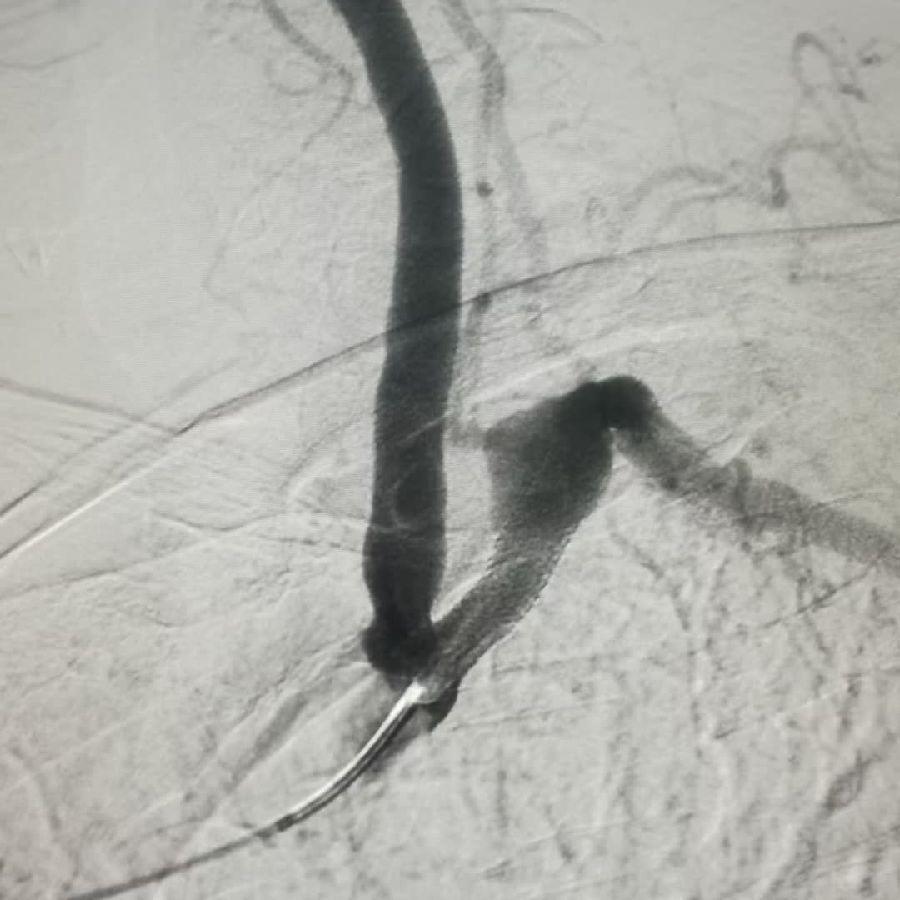

脑梗是它,多年的偏头痛原因竟也是它!

2019-10-25

656阅读